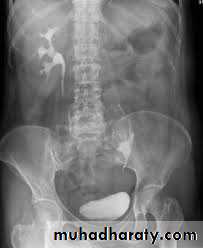

BPH with elevated bladder base

Ca Bladdermissing part of bladder in cystogram stage